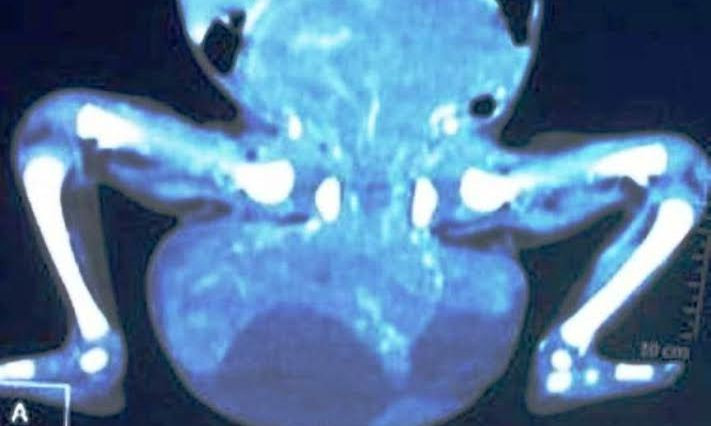

Khối u quái lớn ở vùng cùng cụt của cháu bé sơ sinh 20 ngày tuổi khi chưa phẫu thuật nhìn qua hình chụp phim âm bản.

Tại đây, bệnh nhi được điều trị tích cực, nâng cao thể trạng và làm các xét nghiệm tiền phẫu. Khối u vùng bụng chậu qua kiểm tra bằng CTscan có kích thước lớn: 5,7x12,9x16,7cm; bên trong chứa mô đặc, mô mỡ, nang dịch được nuôi dưỡng bởi nhiều mạch máu. Mới đây, ê kíp phẫu thuật gồm PGS-TS Phạm Như Hiệp, Giám đốc Bệnh viện T.Ư Huế, cùng các bác sĩ khoa Ngoại nhi - Cấp cứu bụng, khoa Gây mê Hồi sức A đã phẫu thuật trong 3 giờ đồng hồ để cắt bỏ toàn bộ khối u có trọng lượng 1,7kg khỏi cơ thể cháu bé.